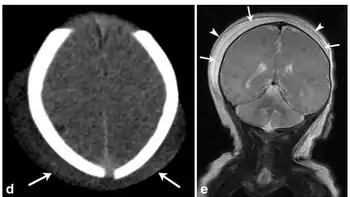

d)Axial CT image in a male infant with history of traumatic delivery demonstrate scalp soft tissue overlying bilateral parietal regions and crossing the sagittal suture e) demonstrates a deep subaponeurotic scalp fluid collection crossing the sagittal suture and extending anteriorly into the right temporal region, consistent with subgaleal hematoma, superficial overlying fluid collection with a similar distribution also noted; collection is within the subcutaneous fibrofatty tissues superficial to galea aponeurosis and is consistent with caput succedaneum